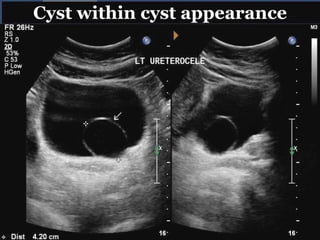

ULTRASOUND:

 Typical findings-dilated upper pole with ureteral

dilation or dilated single system.

 Bladder images differentiate ureterocele from ectopic

ureter- thin-walled cystic dilation within the bladder,

not extending beyond its walls.

Cyst within cyst appearance